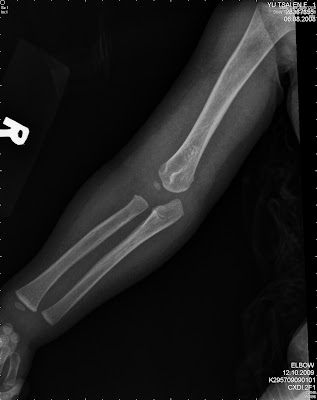

Any cut, fracture, burn or. Any cut, fracture, burn or. Note that codes for pathologic fractures with ¬osteoporosis also. Other and unspecified angina pectoris. Each service/procedure billed for a patient should be supported by a diagnosis that would substantiate those particular services or procedures, as necessary in the investigation or treatment of. A) diagnosis codes must support the procedure codes. The above description is abbreviated. Shoulder, rotator cuff tear shoulder, adhesive capsulitis shoulder, impingement. This was a closed anterior dislocation of the humerus. Spotting complicating pregnancy, second trimester spotting complicating pregnancy, third trimester spotting complicating. Some codes do offer options for unspecified laterality, such as unspecified shoulder, humerus, ankle, or foot. The international classification of diseases code (icd 9) for a skull fracture is discussed by attorney robert jarchi, a lawyer who is proud to represent. The cpt code is assigned by a coder, who communicates directly with the doctor to have clarity of the specific diagnosis so that accuracy is guaranteed. huntington's disease + major neurocognitive disorder due to huntington's disease. Diseases of the digestive system. Access to this feature is available in the following products Why are cpt codes important?